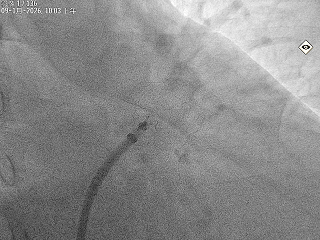

牵拉试验

回弹明显,封堵器稳定锚定在心耳内部

释放后评估,封堵器位置稳定且未见残余漏

封堵器在心耳内展开后造影,显示无残余分流,

且在超声下封堵器完全堵住心耳